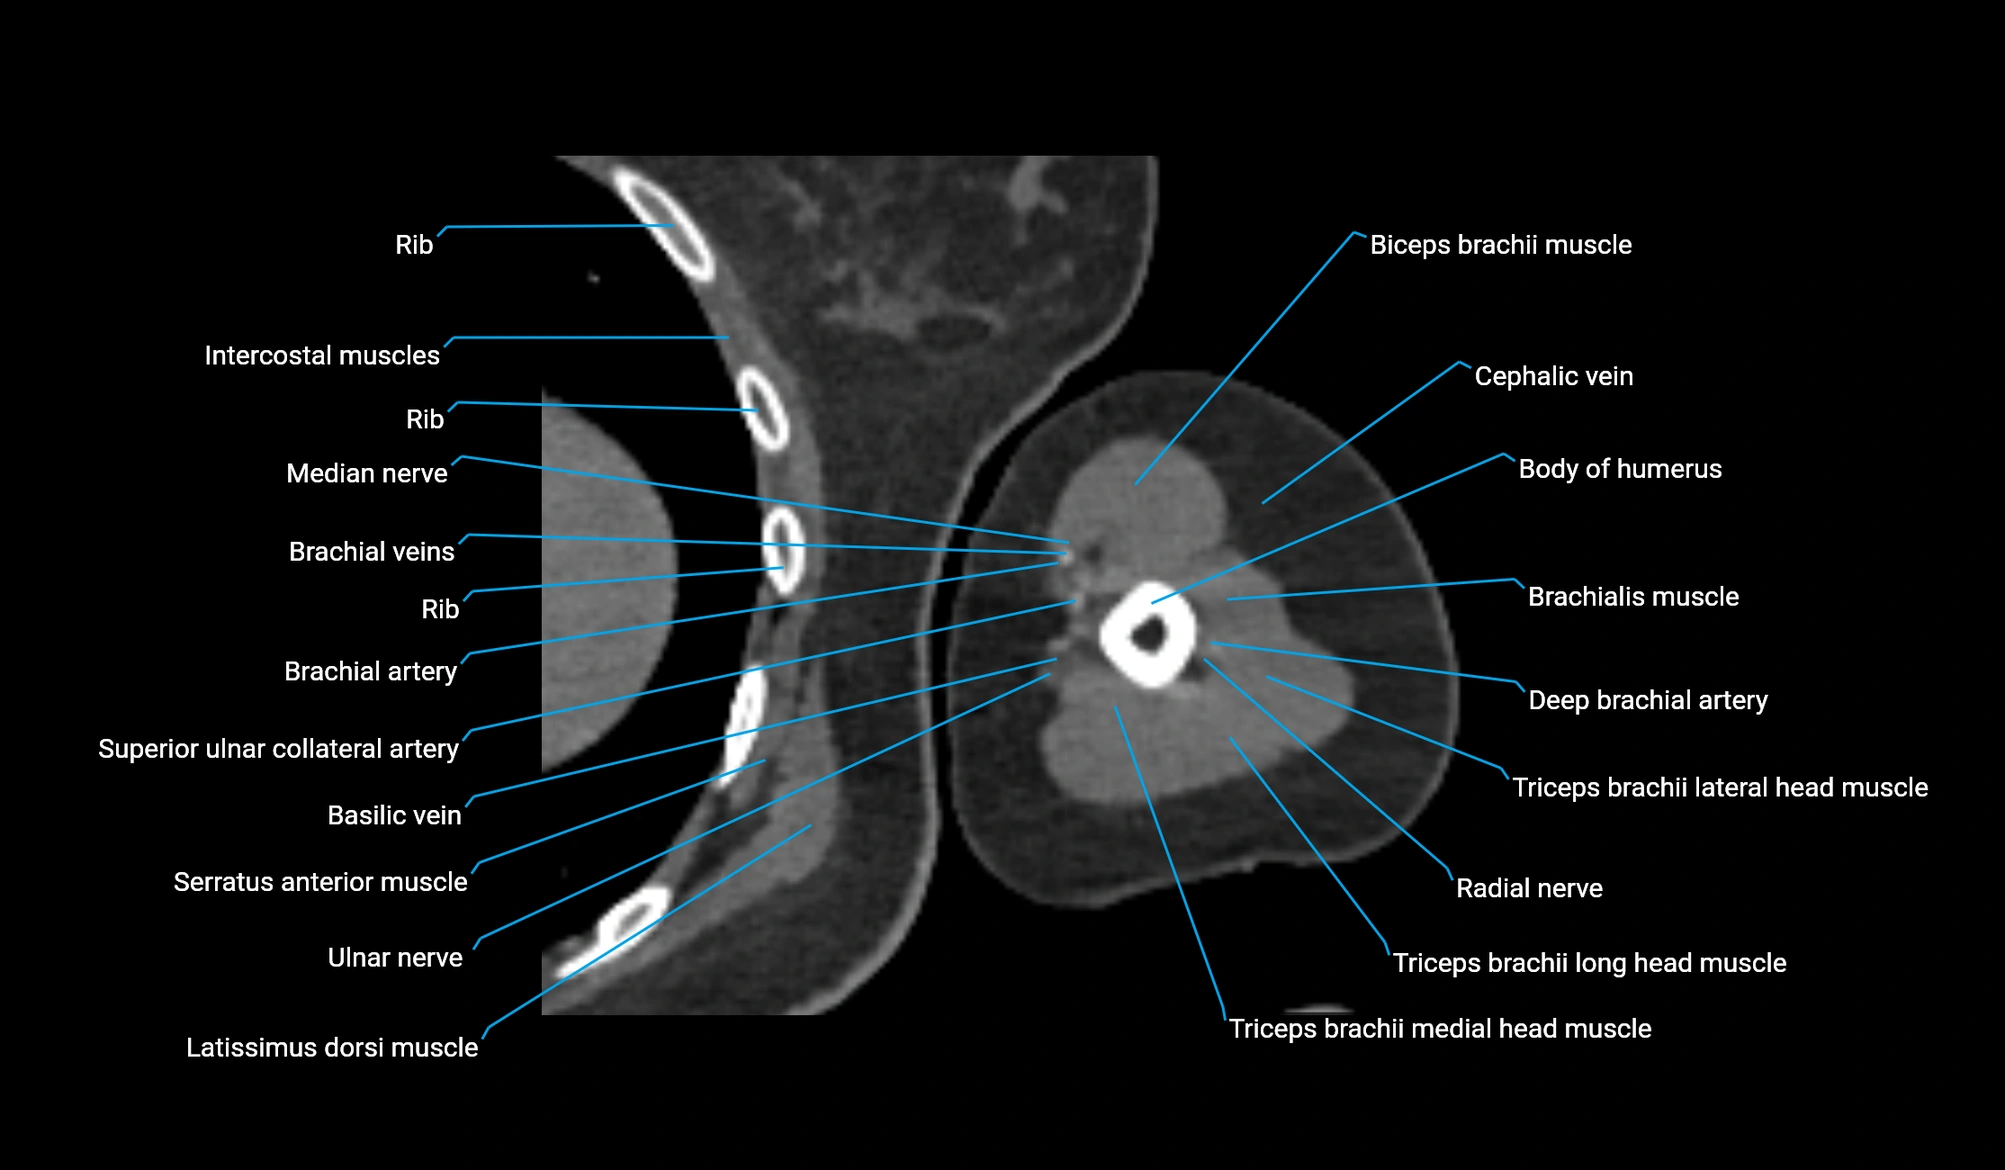

- Body of humerus

- Brachial artery

- Brachialis muscle

- Brachioradialis muscle

- Cephalic vein

- Deep brachial artery

- Long head of triceps brachii muscle

- Medial head of triceps brachii muscle

- Median nerve

- Radial nerve

- Superior ulnar collateral artery

- Triceps brachii muscle

- Ulnar nerve